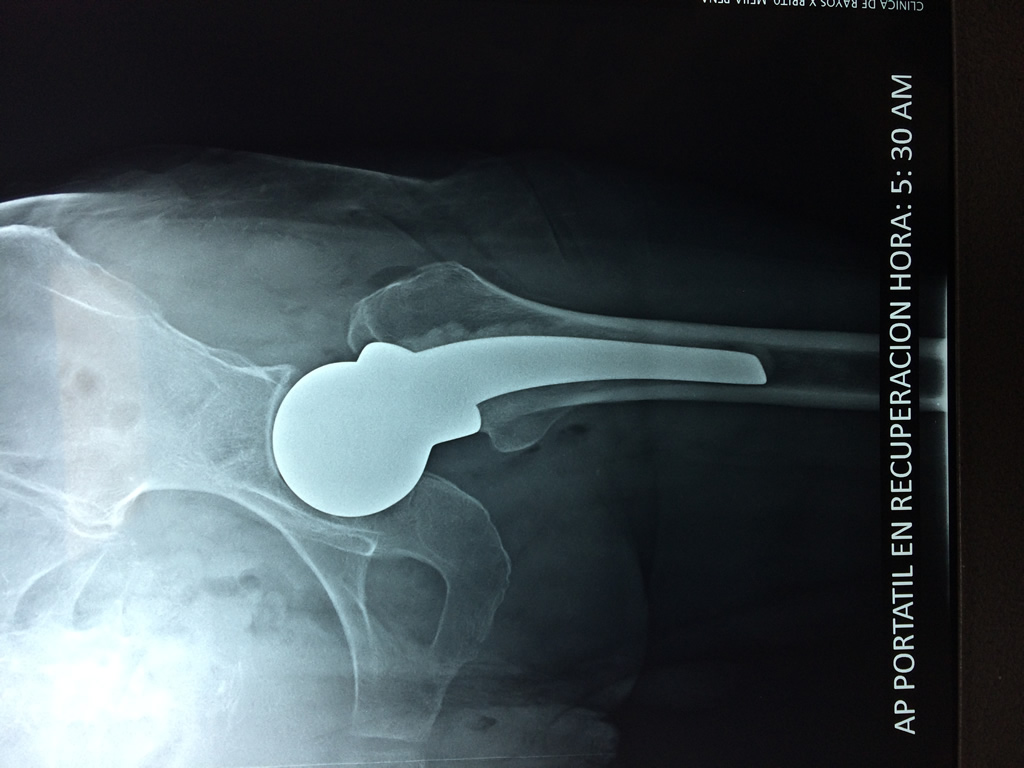

La cirugía de fractura de cadera se realiza para reparar una ruptura en la parte superior del hueso del muslo. Este hueso se denomina fémur.

A menudo se recomienda la cirugía para reparar la fractura debido a dichos riesgos.